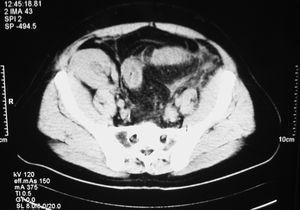

Durante el ingreso se instauró tratamiento médico y antibiótico empírico de amplio espectro, sin mejoría clínica. Los coprocultivos, parásitos y toxina de C. difficile en heces resultaron negativos, al igual que la antigenemia, la PCR y el cultivo de CMV5. La tomografía axial computarizada (TAC) abdominal sin contraste (figura 1 y figura 2) mostró imágenes compatibles de colitis aguda recto-sigma. Ante la sospecha de posible proceso vascular, se solicitó estudio de anticoagulación, homocisteína y anticuerpos anticardiolipina, que fueron negativos, y se inició tratamiento con heparina de bajo peso molecular.

Figura 2. Tomografía axial computarizada abdominal.